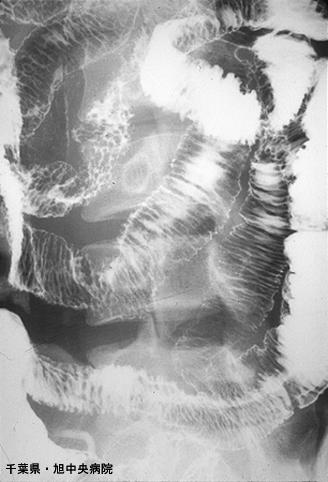

미만성의 조대한 점막면과 궤양을 동반한 소장 아밀로이드증(증례제시:치바현, 아사히중아병원)

염증성・궤양성 질환/소화관 유전분증

소장/2개 이상

X-P